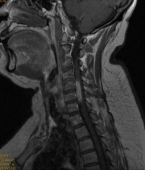

1.颈椎前路减压融合技术

颈椎前路减压融合术适用于①屈曲型颈椎骨折或骨折脱位所致的颈椎创伤性不稳定;②颈椎爆裂性骨折,椎体粉碎,压迫脊髓或脊髓前动脉,产生脊髓前综合征,需做前路减压,解除脊髓受压。③后路广泛性椎板切除,颈椎不稳,经后外侧融合仍不牢固。目前我科已成功开展前路ACDF技术、ACCF技术、ROI-C插片技术、Zero-P零切迹技术,具有创伤小、恢复快、疗效佳,早期下床活动的优点。